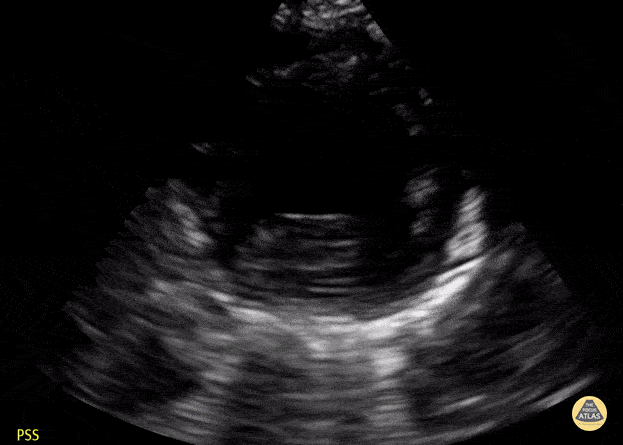

Normal Toddler PSSA apex. Contributor: Jaron Smith, MD, Phoenix Children's Hospital

View: Unspecified Parasternal Long Axis Parasternal Short Axis Apical Four-Chamber Subcostal Four-Chamber Subcostal Inferior Vena Cava Right Upper Quadrant Left Upper Quadrant Suprapubic Longitudinal Suprapubic Transverse Subxiphoid Anterior Thoracic Phrenic